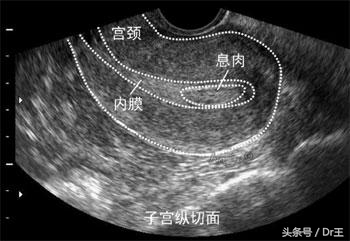

慢性子宫内膜发炎很少有明显的症状,有时顶多来个腹痛腹胀或白带多或不正常出血,不过那时大家都会想是骨盆腔发炎或阴道炎等等,很少会直接想到是内膜发炎,若真的是内膜发炎,也不认为它是大病,服服药就可以过关。又加上内膜是在子宫内,所以不易发现它的异常,更增加大家的轻忽,这里要强调的就是单靠超声波,不管阴式或腹式,来诊断是很不准确的。

要诊断是否有内膜发炎有两个方法,一个是作括除手术,看内膜有没有发炎细胞(plasma cell)准确性很高,但说到括除,太麻烦了,病人也会怕,所以目前建议作软式子宫镜检查,它很简单,不用上麻醉,快的话,10分钟内就可完成检查,准确度可达,但这要靠医师的经验。以前不孕医生都在失败后才要求作这一项检查,现在则建议提早作,我也是这样认为,一切检查都稿定了才上路比较是对的作法。

很多女性都认为输卵管摄影就足以诊断子宫腔是否正常,其实这是错的,要了解子宫腔,非作软式子宫镜不可。